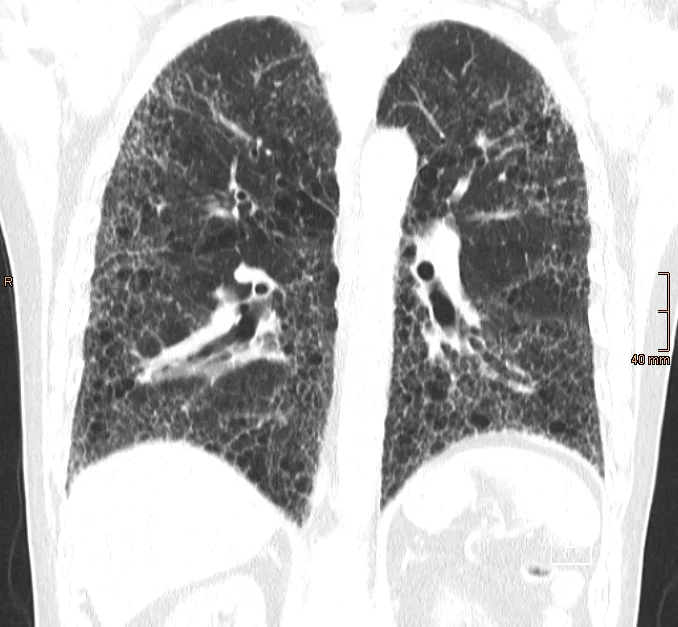

Der radiologischen Bildgebung mittels HRCT ist hierbei von zentraler Bedeutung. Es handelt sich hierbei um eine spezielle Form der Computertomographie (CT), bei der besonders hoch aufgelöste Bilder und dünne Schichten der Lunge erstellt werden. Als "Honeycombing" (Honigwabenmuster) wird hierbei ein fortgeschrittenes Stadium der Erkrankung beschrieben, bei dem das Lungengewebe durch Vernarbung so stark verändert ist, dass es einer Honigwabe ähnelt.

Man sieht hier das typische Bild einer IPF (idiopathischen Lungenfibrose) mittels HRCT und dem klassischen UIP-Muster: supleurale und basale Prädominaz, retikuläre Veränderungen, Honigwaben ("Honeycombing"), Traktionsbronchiektasen